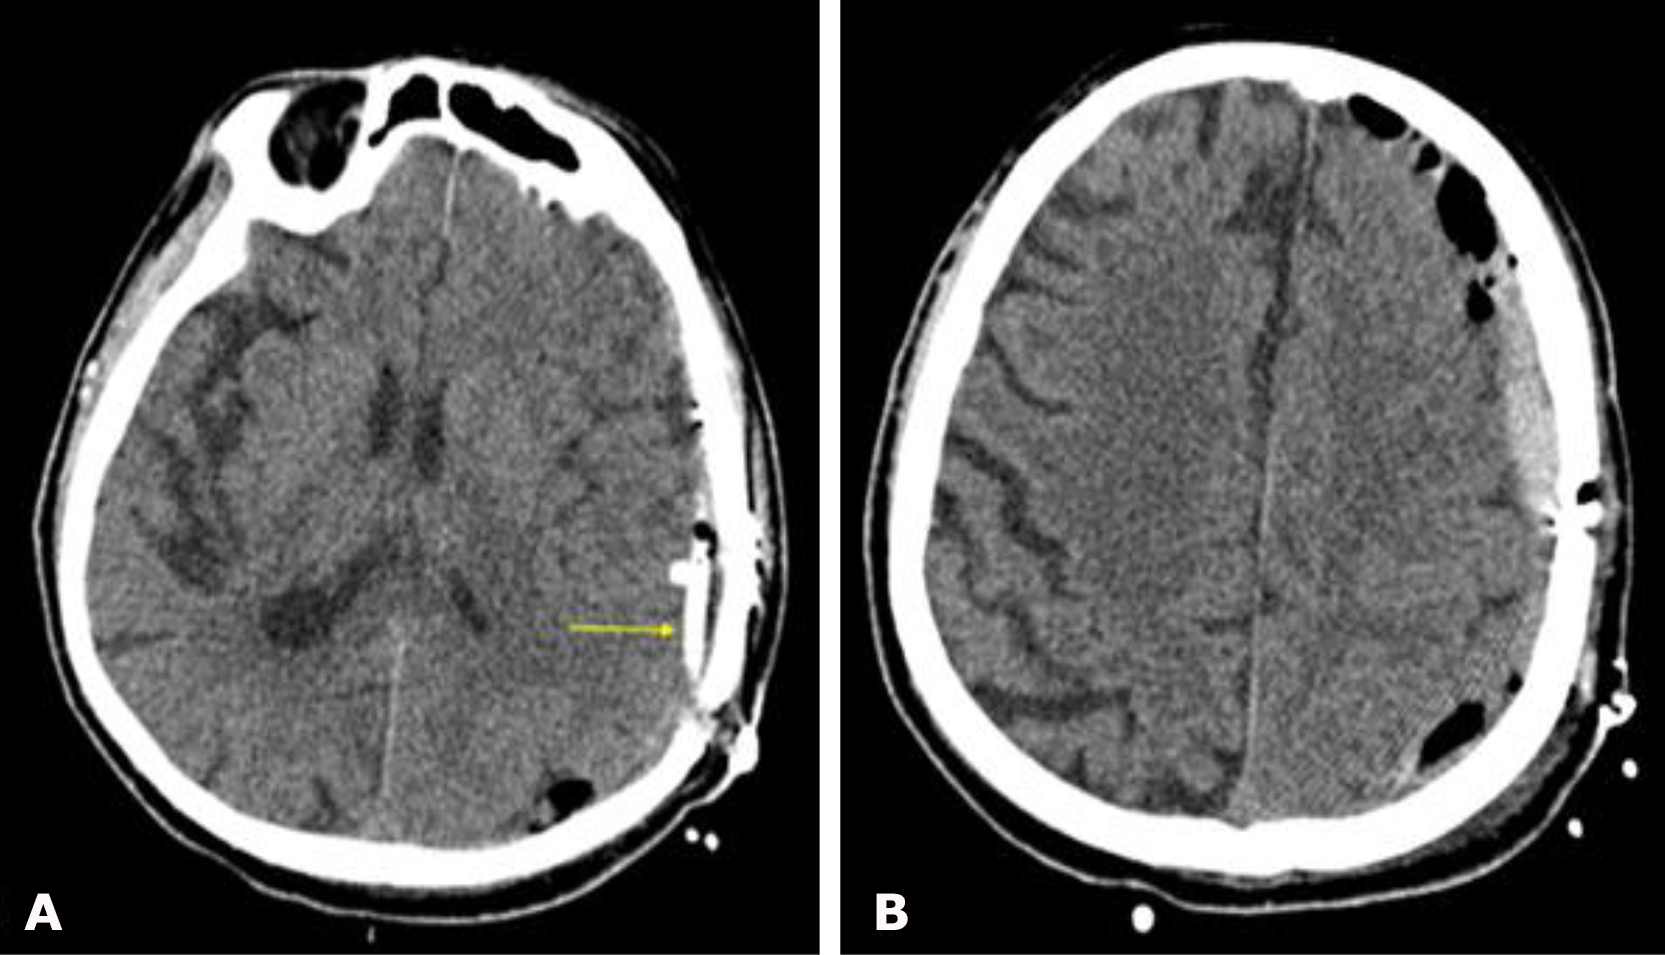

Non-contrast brain CT revealed bilateral chronic subdural hematomas (cSDH) in the frontal regions. The hematoma dimensions (thickness/length/height) were 8/48/48 mm on the left and 9/132/51 mm on the right. No displacement of the midline structures of the brain was detected (Fig. 1).

Fig. 1. Preoperative brain CT: A, B—axial projections demonstrating bilateral frontal cSDH (indicated by red arrows)

The postoperative course was uneventful. The neurological status remained unchanged, and no complications were observed. The patient was discharged from the hospital on postoperative day 2. Follow-up brain CT performed 1 month after surgery (Fig. 4) demonstrated complete resolution of bilateral frontal cSDH. At follow-up examination, regression of global cerebral symptoms was noted.

Fig. 4. Postoperative brain CT: A, B – axial projections. Purple arrows indicate the radiopaque embolic agent Onyx™ within the projections of the left and right MMAs